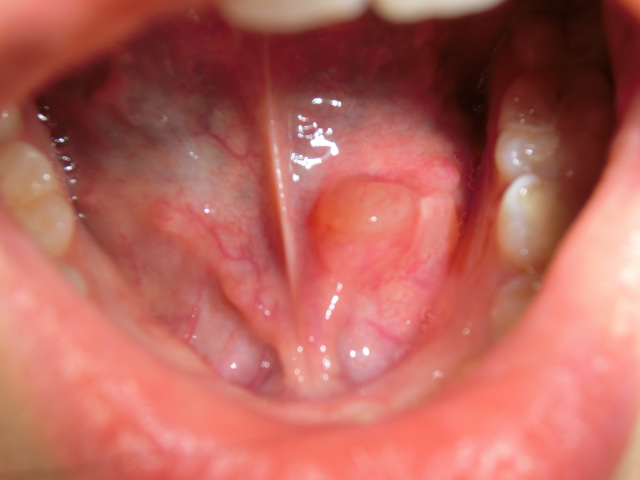

舌下型では、口腔底粘膜が押し上げられ膨隆が目だちます。

大きくなると粘膜を通して内容物がみえるようになります。

舌と下あごの間の粘膜が風船のように腫れます。